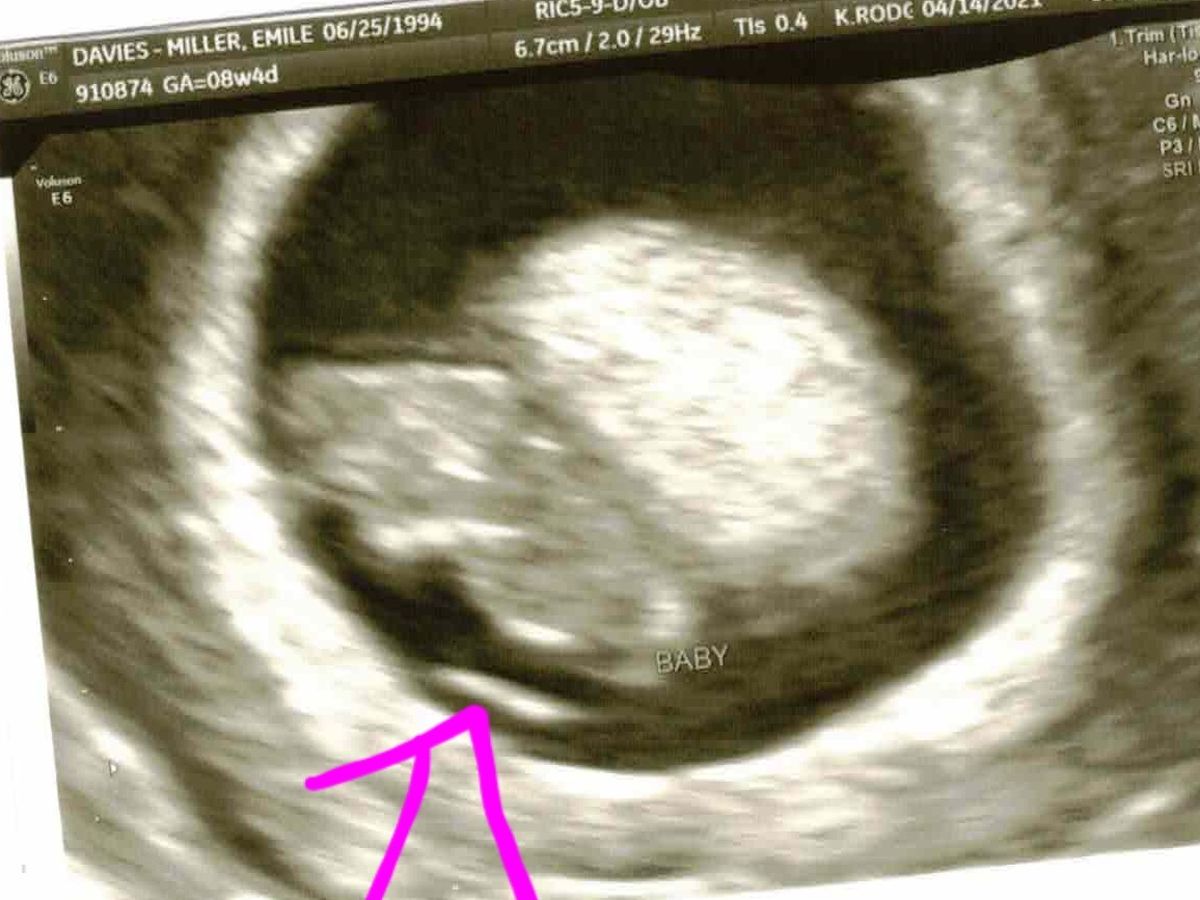

Today I went in to my 16 week OBGYN appointment excited to see my baby for the first time in two months. After a grooling ultrasound it came to the attention of my doctor that my baby had skull abnormalities and she rushed me to see a specialist.

Four hours later we have learned that our baby has Anencephaly or a baby with an underdeveloped brain and incomplete skull. A baby born with anencephaly will only survive a few days after birth. After hearing this diagnosis the doctor provided me my options. Abortion will not be covered by my health insurance as the baby can still be brought to full term so health insurance will not take a stance politically to allow me to abort my baby with a death sentence.